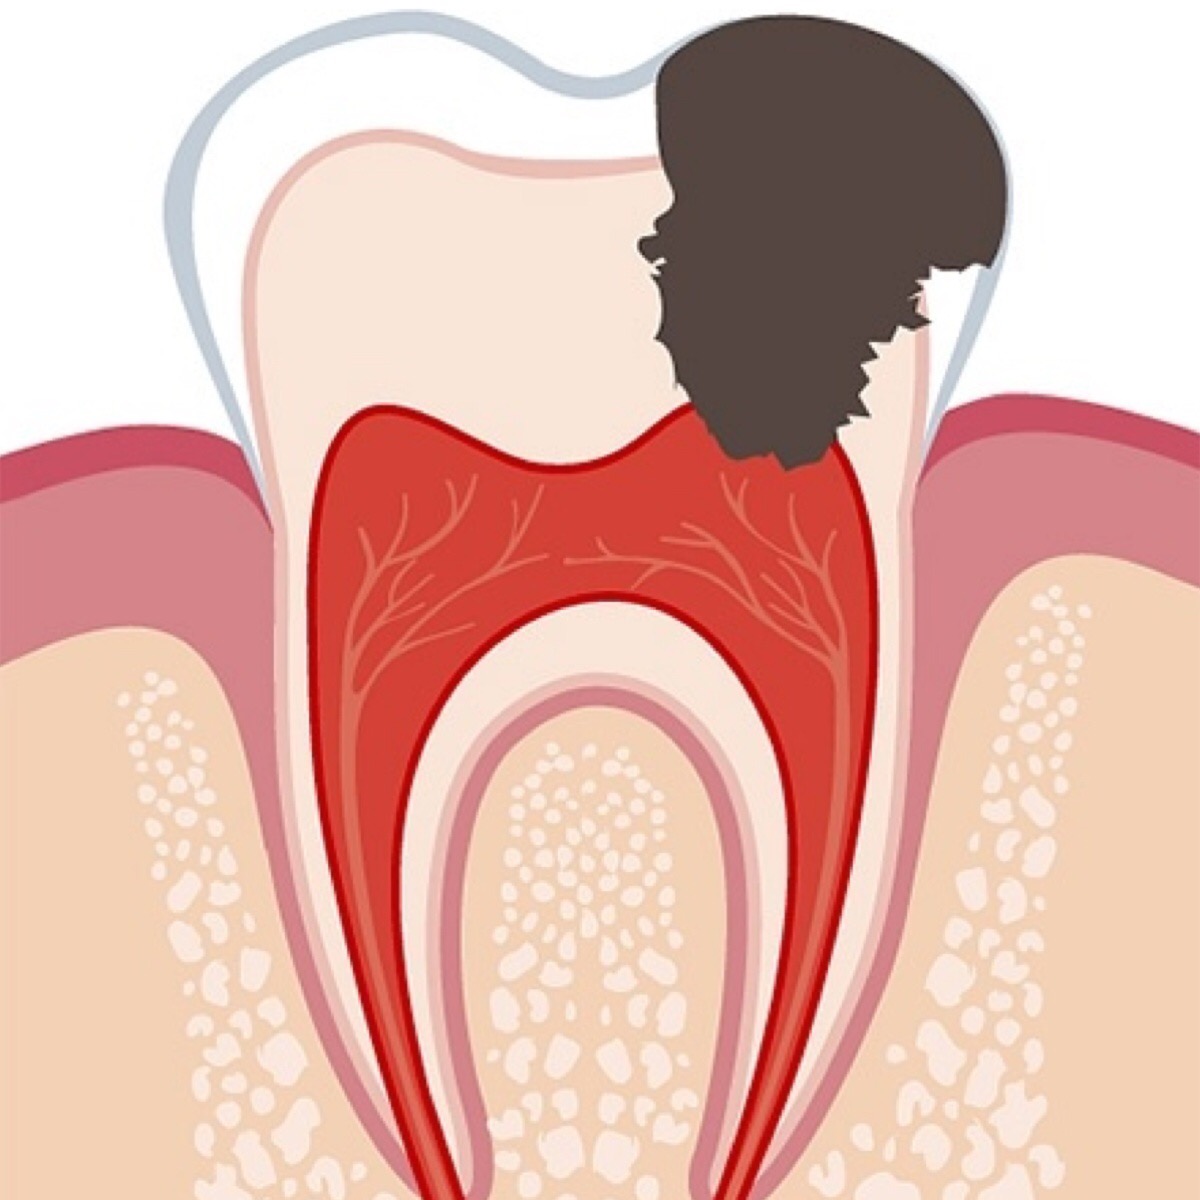

3. Средний кариес - кариозный процесс полностью прошел всю толщу эмали и попал в поверхностные слои дентина. Скорость распространения патологического процесса в разы быстрее из-за анатомии дентина. Симптоматика не отличается от поверхностного.

4. Глубокий кариес - процесс затрагивает глубокие слои дентина и движется по направлению к пульповой камере. Значительная полость, кратковременные боли от физических и химических раздражителей, проходящие сразу после их удаления.

Поэтому, когда у пациента есть боль, то это либо прыжок в максимально глубокий кариес, либо уже вскрытие полости нерва из-за размягчения всех слоев дентина, то есть осложнение кариеса - пульпит.

Предсказать реальную глубину процесса сложно, даже по кт. Если полость отчётливо видна уже на рентгене, то ничего хорошего ждать не стоит. Но зуб - это живая единица, и при длительном процессе полость нерва изменяет свою анатомию и "прячется" глубже.

То есть, вырабатывается вторичный дентин, который защищает зуб от процесса. И вроде бы, согласно анатомии, этот самый процесс уже должен был давно вскрыть полость нерва, но нет - иногда оказывается, что это лишь глубокий кариес.

А теперь об осложнениях кариеса. Это пульпит - тот момент, когда бактерии попали в полость зуба, которая заполнена сосудами и нервами.

И периодонтит, наступает после гибели полости нерва и заключается в воспалении связки зуба. Треды в разработке.